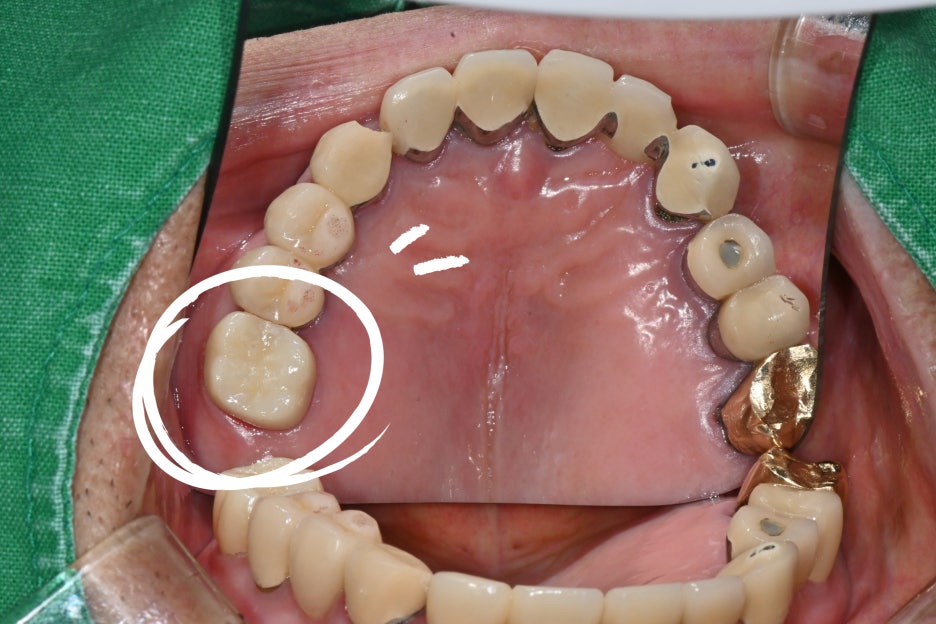

Recently, a male patient in his 60s and older

visited us with the symptoms that “last night, during a meal, my molar crown came off,

and the pain is severe.”

It initially appeared to be a simple crown detachment,

but after a detailed examination, the situation was much more complicated.

Inflammation had progressed deeply inside the molar,

and the damage had reached the nerve (pulp).

The patient’s molar had decay progressing beneath the restoration,

damaging the tooth up to near the root,

so root canal treatment was essential.